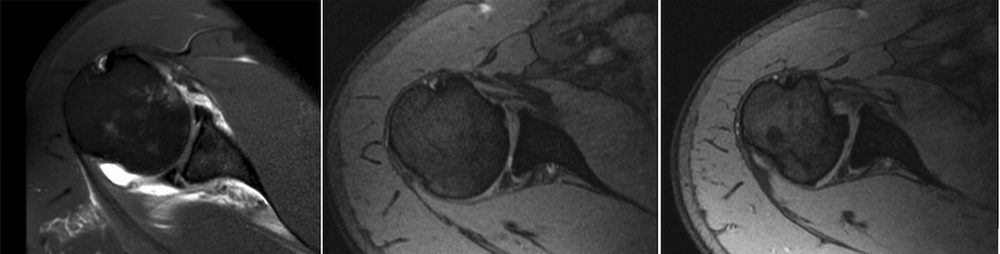

<p>O diagnóstico é baseado em uma combinação de história clínica, exame físico e exames de imagem. Testes específicos durante o exame físico, como a manobra de abdução com rotação externa do ombro, podem reproduzir os sintomas. Exames de imagem, como a ressonância magnética ou a angiografia por tomografia computadorizada, são úteis para visualizar a compressão do nervo e da artéria e avaliar a presença de qualquer anomalia anatômica. A condição pode ser subdiagnosticada e não valorizada em exames de imagem se não houver fraqueza clínica significativa.</p>

<p><strong>Exemplo de Laudo de Ressonância:</strong>

"Observa-se atrofia do músculo redondo menor, sugerindo possível compressão crônica do nervo axilar no espaço quadrangular."</p>

<p>Exemplo de arteriografia (exame para ver o fluxo arterial) de paciente com síndrome do espaço quadrangular. As imagens mostram o fluxo normal e como ele é afetado ao mover o ombro</p><p>Imagens: (a) Fluxo normal no ombro direito em posição neutra; (b) Compressão da artéria no ombro direito ao levantar o braço em abdução e rotação externa (posição de arremesso); (c) Fluxo normal no ombro esquerdo em posição neutra; (d) Fluxo normal no ombro esquerdo ao levantar o braço em abdução e rotação externa (posição de arremesso).</p>